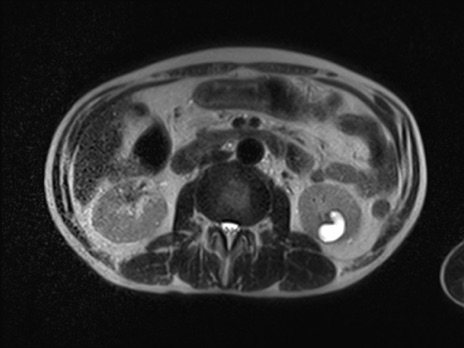

【腹部TIPS】症例38 参考症例 MRI (T2WI横断像)

60歳代男性

MRI